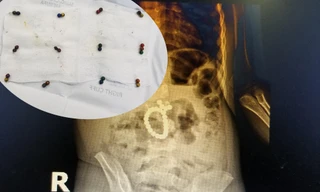

TPO - Bệnh viện Sản nhi Nghệ An vừa phẫu thuật, cấp cứu cho một bé N.T.T (3 tuổi, trú tại TP Vinh) bị thủng tá tràng, ruột do nuốt phải 25 viên bi nam châm.

Đến Bệnh viện Đa khoa MEDLATEC khám trong tình trạng đau bụng nhiều ngày không rõ nguyên nhân, gia đình bé vô cùng sững sờ biết nguyên nhân con có nguy cơ thủng ruột. May mắn bé được ê-kíp cấp cứu của bệnh viện xử trí kịp thời, qua cơn nguy kịch.